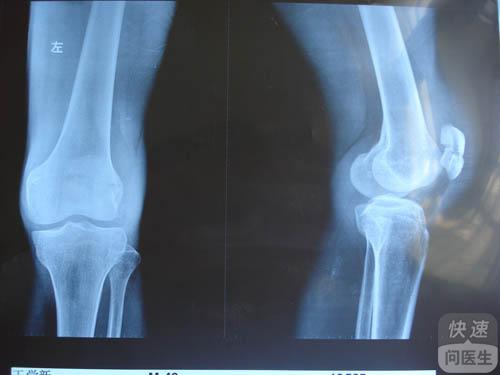

核心提示:膝关节炎是一种以退行性病理改变为基础的疾患。多患于中老年人群,其症状多表现为膝盖红肿痛、上下楼梯痛、坐起立行时膝部酸痛不适等。也会有患者表现肿胀、弹响、积液等,如不及时治疗,则会引起关节畸形,残废。跟...